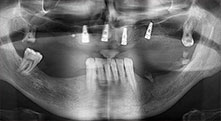

For what indications do you use the saws?

Bratu: We routinely use the instruments for harvesting bone blocks and splitting alveolar ridges. We also use the Piezomed B6/B7 for osteotomy of impacted teeth and removing failed implants. All indications that require deep, clean cuts.